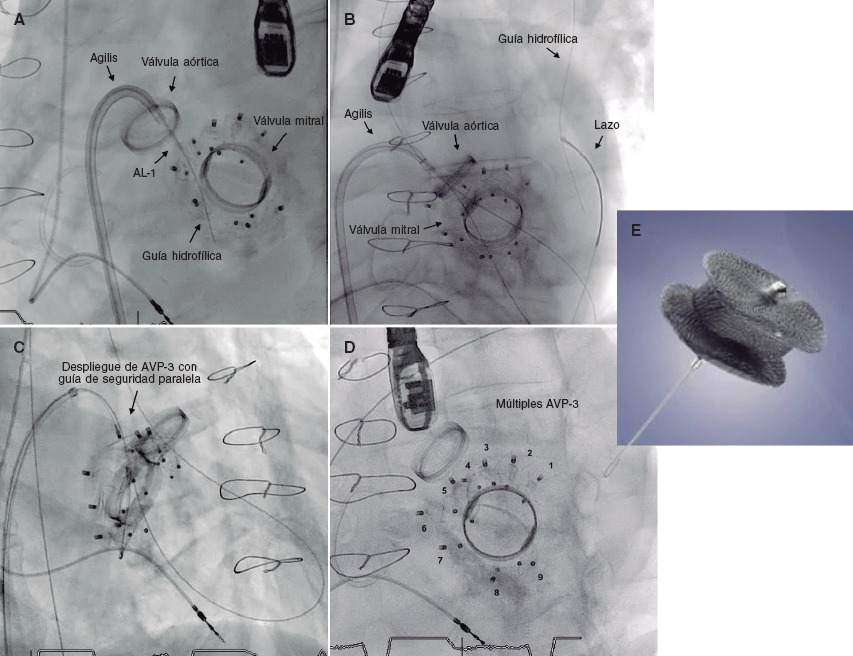

Tres meses después ingresó con insuficiencia cardiaca en clase funcional III-IV de la New York Heart Association (NYHA) y anemia hemolítica, con múltiples fugas paravalvulares mitrales cuantificadas como insuficiencia grave. En sesión médico-quirúrgica se decidió realizar tratamiento percutáneo debido al alto riesgo quirúrgico del paciente. Para los procedimientos médicos y utilización de información clínica anónima se obtuvieron los respectivos consentimientos informados. Se llevó a cabo el cierre percutáneo de la fugas con implante de 7 dispositivos Amplatzer Vascular Plug III (figura 1E), quedando mínimas fugas residuales.

Figura 1.

Se realizó un abordaje percutáneo. Vía punción transeptal se construyó un circuito venoarterial anterógrado con guía hidrófila de 0,035 pulgadas (figura 1A,B) (vídeos 2 y 3 del material adicional) y se implantaron 2 dispositivos Amplatzer Vascular Plug III de 12/5 mm (figura 1C) (vídeos 4 y 5 del material adicional), finalizando con 9 dispositivos del mismo tipo rodeando la circunferencia protésica (figura 1D y figura 2D) (vídeo 6 del material adicional). El procedimiento se finalizó sin complicaciones. La ecocardiografía transesofágica durante la intervención mostró una reducción de las fugas paravalvulares mitrales, cuantificadas como insuficiencia leve (figura 2C) (vídeo 7 del material adicional). El paciente evolucionó favorablemente, lo que posibilitó el alta hospitalaria en clase funcional NYHA II-III, con corrección de la anemia (hemoglobina de 12 g/dl) y seguimiento ambulatorio.